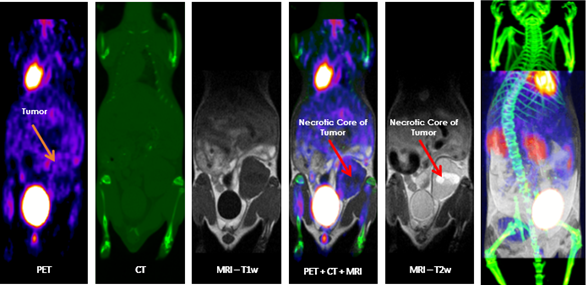

Multimodal Imaging: Multimodal imaging combines the strength of MRI with other imaging modalities such as PET and CT. PET provides information on the spatial distribution of molecular signal of interest. In this case MRI confirmed that the absence of tracer uptake in the center of the images was due to the presence of a necrotic core, which appears hyperintense on T2-weighted MRI. Image Credit: Scintica Instrumentation Inc

Multimodal imaging

According to current preclinical imaging trends, multimodal imaging can provide synergistic information on a particular disease model or response to a target compound, and it should be considered in all studies wherever feasible. The SimPET insert can be integrated with the M-Series to enable simultaneous PET/MRI.

Alternatively, the animal can be transported to different imaging modalities using a multimodal imaging cassette to fit inside the MRI coil on the M-Series. These images can be co-registered using third-party software like VivoQuant.

Multimodal imaging combines the strength of MRI with other imaging modalities, such as PET and CT. PET provides information on the spatial distribution of molecular signal of interest. In this case MRI confirmed that the absence of tracer uptake in the center of the images was due to the presence of a necrotic core, which appears hyperintense on T2-weighted MR. Image Credit: Scintica Instrumentation Inc